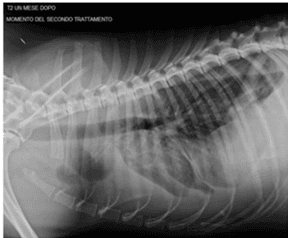

Intra-Articular Administration of Autologous Micro-Fragmented Adipose Tissue in Dogs with Spontaneous Osteoarthritis: Safety, Feasibility, and Clinical Outcomes

Offer Zeira, Simone Scaccia, Letizia Pettinari, Erica Ghezzi, Nimrod Asiag, Laura Martinelli, Daniele Zahirpour, Maria P. Dumas, Martin Konar, Davide M. Lupi, Laurence Fiette, Luisa Pascucci, Leonardo Leonardi, Alistair Cliff, Giulio Alessandri, Augusto Pessina, Daniele Spaziante, Marina Aralla, Stem Cells Translational Medicine, 2018